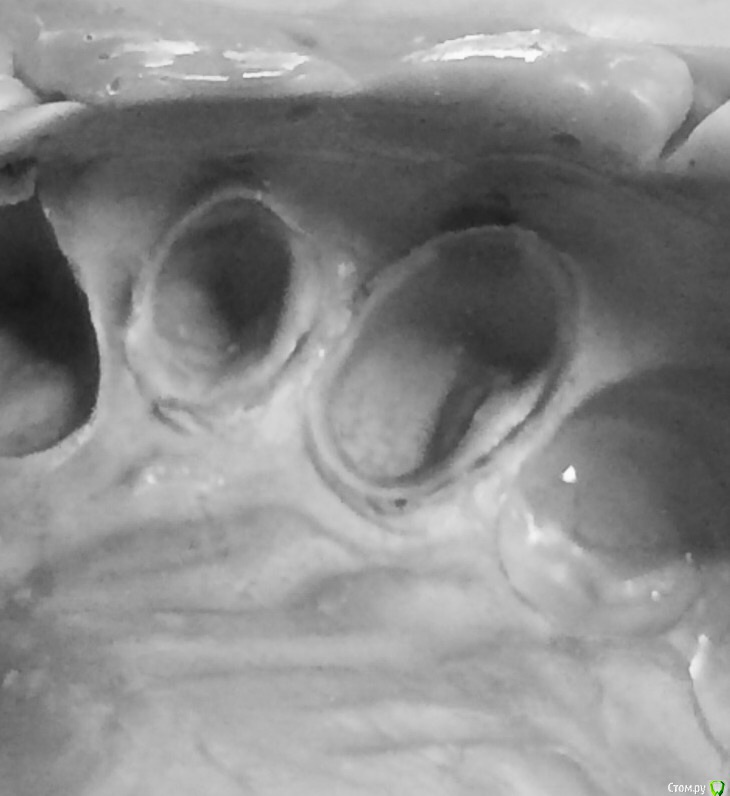

Aquarius Опубликовано 6 февраля, 2015 Поделиться Опубликовано 6 февраля, 2015 (изменено) Наносил только на зубы.так что предложенная методика сработала. Жаль,что пора во вкладке обнаружилась на клыке,пришлось выкручиваться.image.jpgПростите конечно, но на мой взгляд слепок не айс. Зауступное оторвано на двойке и тройке. Чуть больше корреги кладите. И чуть более вертикально вносите ложку Изменено 6 февраля, 2015 пользователем Aquarius Ссылка на комментарий

chervoncevdaniil Опубликовано 6 февраля, 2015 Поделиться Опубликовано 6 февраля, 2015 Тоже хотел написать что на тройке зауступное медиально вообще не проснято,но думал может фото такое и с телефона плохо видно Ссылка на комментарий

Larnary Опубликовано 6 февраля, 2015 Поделиться Опубликовано 6 февраля, 2015 Пора в самой вкладке оказалась,а не в слепке. И мне пришлось вытачивать вогнутость во вкладки,чтобы ее убрать. Да и на 2 с неба небольшой дефект от вкладки в виде ступеньки. Но пои данной методике все эти элементы проснулись.А что касается зауступного,то это мой недочет,а не методики. Если вы читали выше, у меня до этого вообще не получались одномоментные слепки без оттяжек. А по этой методике 2 пациентам подряд вполне удовлетворительно. Теперь надо просто опыта набраться и все. Ссылка на комментарий

Larnary Опубликовано 6 февраля, 2015 Поделиться Опубликовано 6 февраля, 2015 (изменено) Aquarius,за советы спасибо но мне кажется зауступное с медиалки всё же проснялосьТолько прошу не обсуждать 2 с небной стороны-косяки в обточке и косяк со вкладкой сам вижу.пытался сгладить,но побоялся сверх широкий уступ сделать,он там и так нехилый вышел. Под дорогую работу такие вкладки заставил бы техника переделать Изменено 6 февраля, 2015 пользователем Larnary Ссылка на комментарий